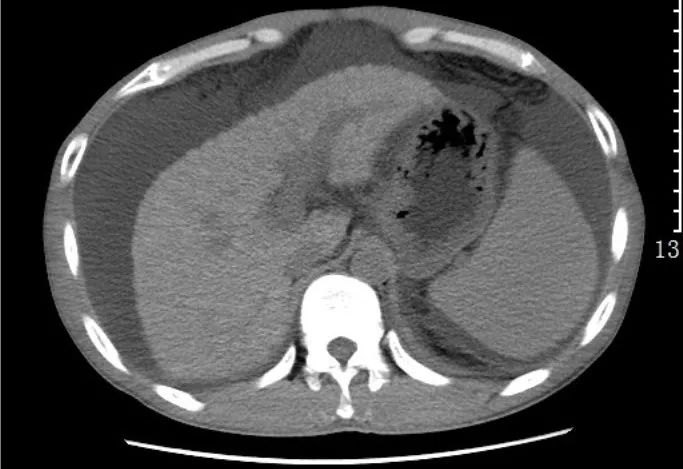

7)肝硬化:是临床常见的慢性进行性肝病,由一种或多种病因长期或反复作用形成的弥漫性肝损害。临床上以肝功能损害和门脉高压症为主要表现,并有多系统受累。

CT表现:肝叶比例失调,肝脏表面高低不平,肝裂增宽,肝脏密度不均匀;继发性改变:脾肿大,腹水,门脉高压(侧支循环形成,脾门、胃底、食管下段静脉迂曲扩张)。